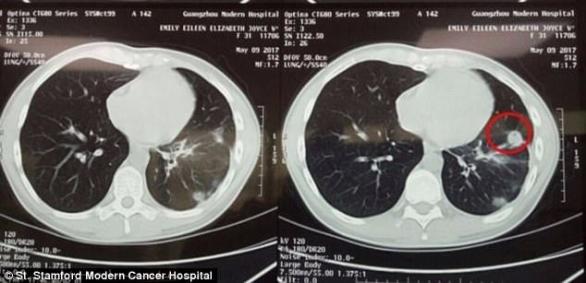

肺癌復查的目的是為了提前發現肺癌復發。而不同的肺癌,復發的概率是大不相同的。和復發有關的因素有以下幾點:1. 小細胞肺癌,還是非小細胞肺癌通常來說,小細胞肺癌,更容易復發,生...